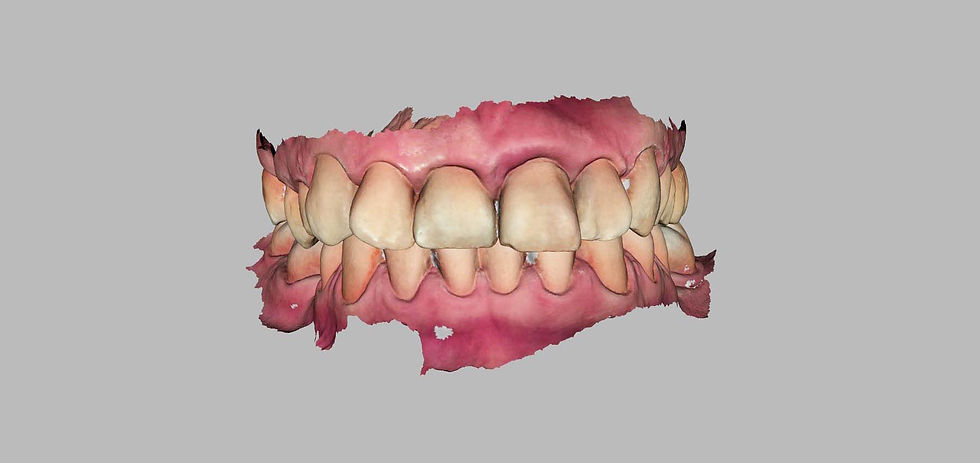

Before the extraction of the fractured element, an intraoral scan is performed for the digital design of the temporary prosthesis, which will be delivered the same day of the surgery.

Design of the temporary crown with CAD software.